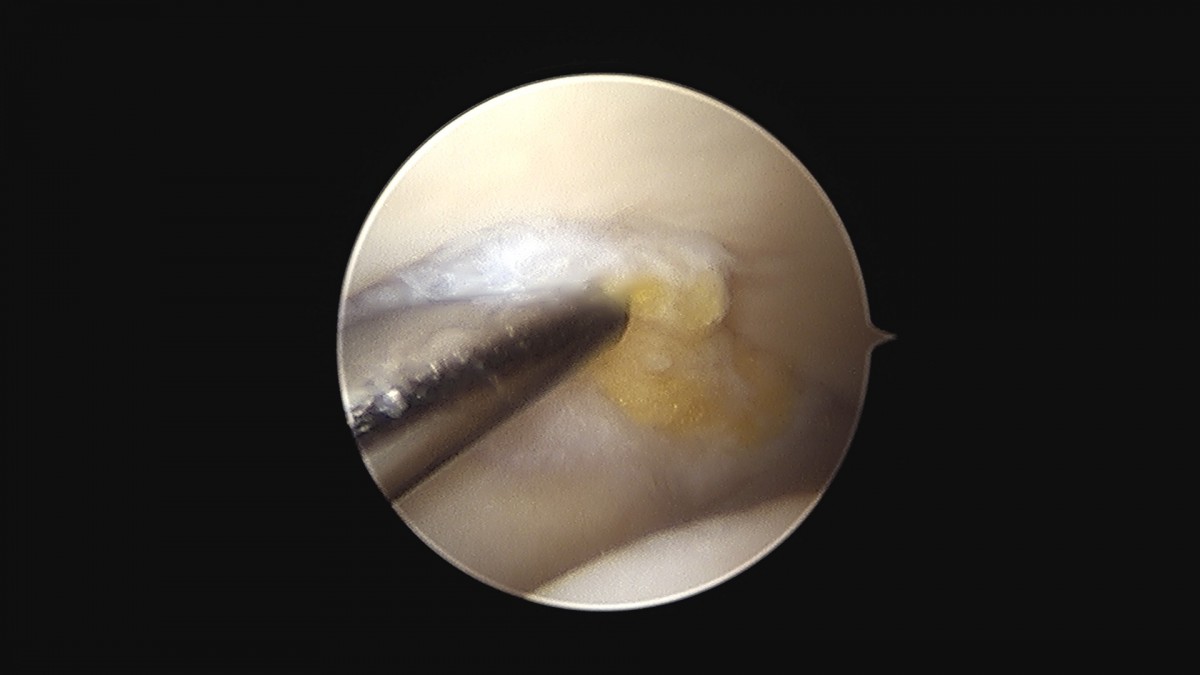

이재상원장님 무릎 변연절제술 권오O 환자

작성자 최고관리자 댓글 0건 조회 373회 작성일 25-09-16 16:11